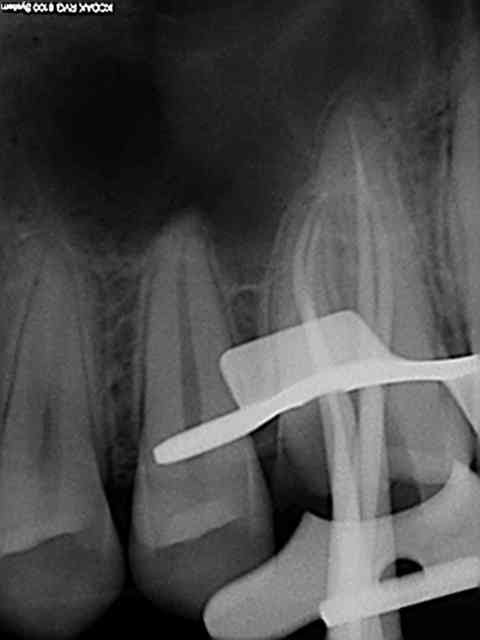

un petit retour sur un traitement canalaire datant de ce matin, voila ma séquence:

-pose de la digue

- dépose du pansement et élargissement Endo -Z

- passage lime 8 10 et 15 et racleur 10 et 15

- radio lime en place

- passage sériel des rotatifs Heroshaper avec lime de cathé entre chaque et rinçage hypochlorite

- Radio cône en place

- Obturation ( finger et Macspadden).

Voila le problème, l'endo ne me satisfait pas, sur les radios lime en place, aucun souci et dès que les cônes entrent dans le jeu tout déraille..

Ou est mon erreur? est ce que j'oublie une étape?

En voila deux supplémentaires, impossible de retrouver la dernière j'ai du l'enregistrer sur un autre dossier, je cherche ça.

On voit bien le cône dans le palatin qui bloque..

A vrai dire c'est surtout le palatin qui me gêne au niveau longueur, je trouve les deux autres pas trop mal (mis a part la condensation que je trouve encore très moyenne..)